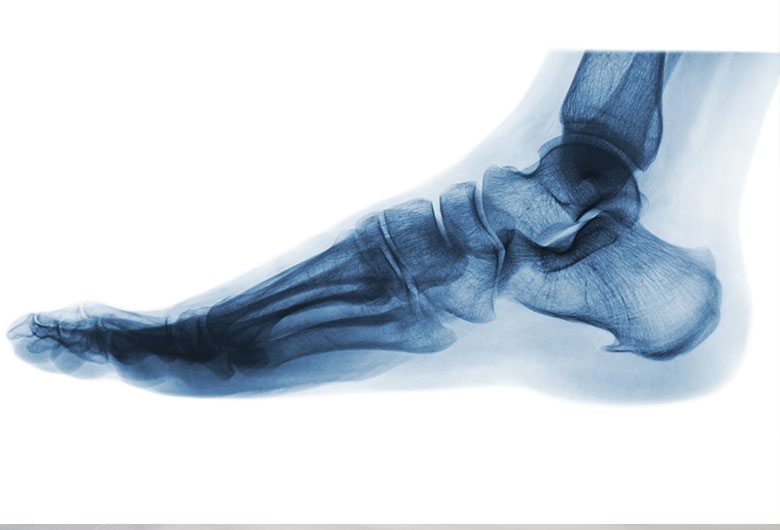

E’ simile a una spina di rosa o a un artiglio, da qui il suo nome “Spina calacaneare”: si tratta di uno sperone osseo anomalo che si sviluppa nella parte posteriore (o inferiore) del calcagno, che è una delle 7 ossa del tarso.

Ne esistono infatti due tipi: la spina calacaneare inferiore, sorge sulla pianta del piede, nell’inserzione della fascia plantare. Patologia spesso associata alla fascite plantare; e la spina calcaneare posteriore: nella parte posteriore del calcagno, a livello dell’inserzione del tendine d’Achille.